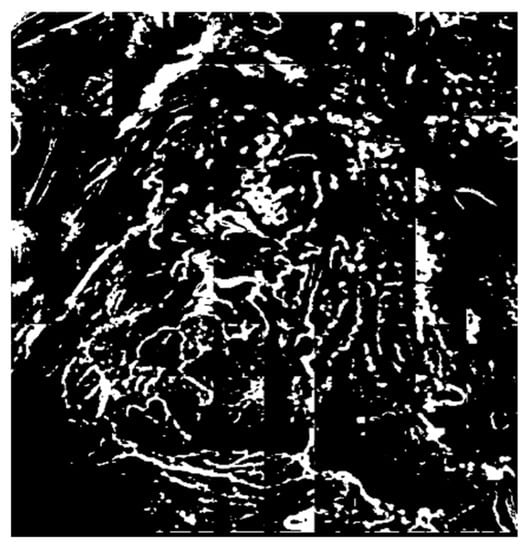

3.2.3. Removal of the Background Area Using the ART2 Algorithm

3.3. Extraction of Object Information from the Microvessel Area